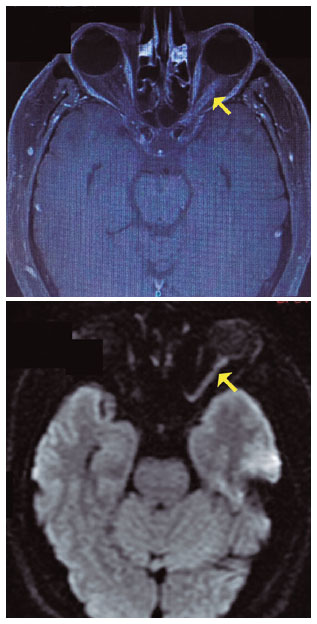

A 58-year-old male patient was referred for neurophthalmic evaluation because of sudden and painless visual loss in the right eye over the preceding 2 months and worsening within a few days before referral. Approximately 1 year earlier, the patient experienced sudden and painless visual loss in the left eye. At the time, MRI scans of the brain and orbit revealed enhancement of the left optic nerve (Figure 1). On the basis of a tentative diagnosis of optic neuritis, the patient underwent intravenous methylprednisolone pulse therapy, but no visual improvement ensued.

T2-weighted MRI revealed hyperintense thickening in both optic nerves that was associated with post-contrast enhancement and mild diffusion restriction, which suggested concomitant inflammatory and ischemic processes in both eyes (Figure 4).